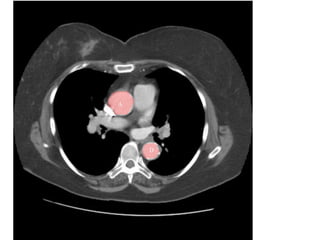

Đm phổi gốc Đm chủ

Case 2: bệnh nhân nam 61 tuổi, nhập viện vì đau ngực và khó thở.

- Siêu âm: dãn buồng tim phải, tăng áp động mạch phổi.

- CT huyết khối động mạch phổi phải và trái.

- Kích thước đm phổi gốc (d = 33 mm) lớn hơn động mạch chủ cùng lát

cắt…nghĩ tắc cấp.

- Điều trị tiêu sợi huyết tại BVTMAG. Đáp ứng tốt.